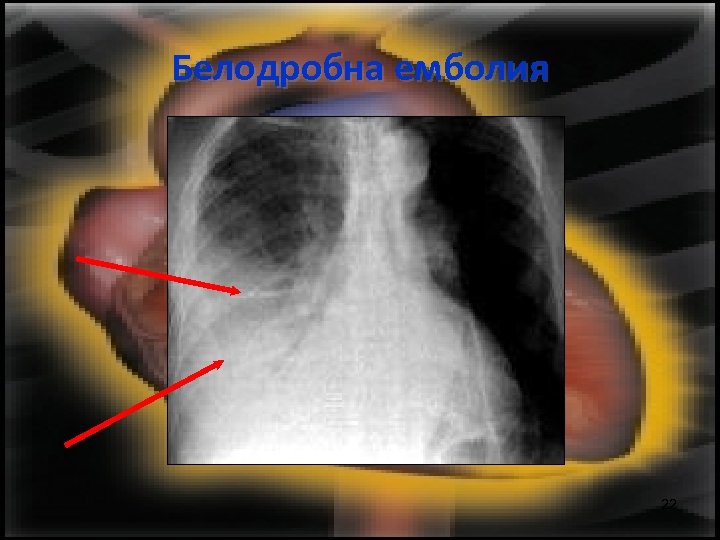

Белодробна емболия 22